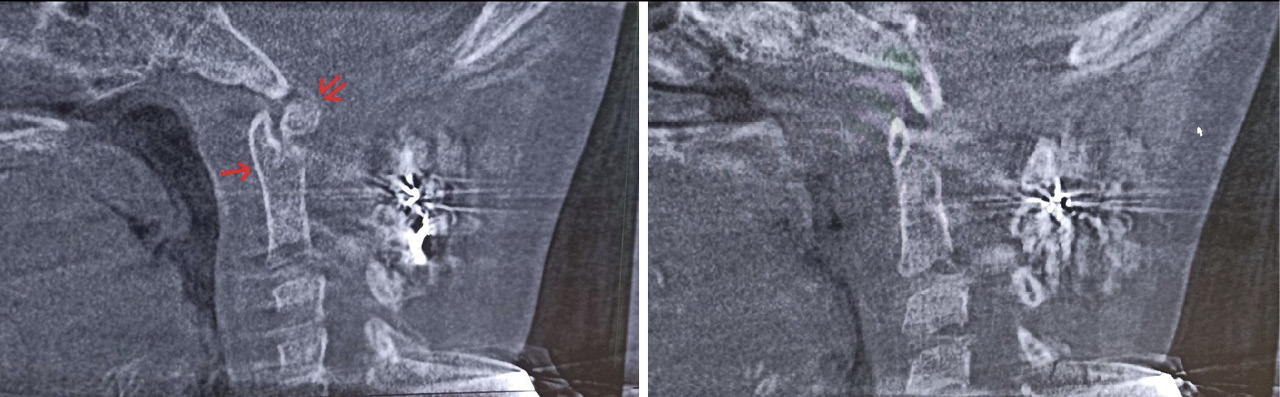

Клиническое наблюдение 1

Рис. 1. Конусно-лучевая компьютерная томография краниовертебральной области, фронтальный срез на уровне зубовидного отростка С2 позвонка. Методика измерения соотношений в латеральных атланто-аксиальных суставах